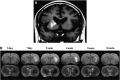

As a sequel of brain ischemia, selective neuronal loss (SNL)-as opposed to pannecrosis (i.e. infarction)-is attracting growing interest, particularly because it is now detectable in vivo. In acute stroke, SNL may affect the salvaged penumbra and hamper functional recovery following reperfusion. Rodent occlusion models can generate SNL predominantly in the striatum or cortex, showing that it can affect behavior for weeks despite normal magnetic resonance imaging. In humans, SNL in the salvaged penumbra has been documented in vivo mainly using positron emission tomography and (11)C-flumazenil, a neuronal tracer validated against immunohistochemistry in rodent stroke models. Cortical SNL has also been documented using this approach in chronic carotid disease in association with misery perfusion and behavioral deficits, suggesting that it can result from chronic or unstable hemodynamic compromise. Given these consequences, SNL may constitute a novel therapeutic target. Selective neuronal loss may also develop at sites remote from infarcts, representing secondary 'exofocal' phenomena akin to degeneration, potentially related to poststroke behavioral or mood impairments again amenable to therapy. Further work should aim to better characterize the time course, behavioral consequences-including the impact on neurological recovery and contribution to vascular cognitive impairment-association with possible causal processes such as microglial activation, and preventability of SNL.